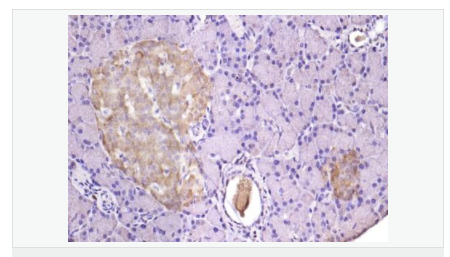

| 產(chǎn)品應(yīng)用 | WB=1:500-2000 ELISA=1:5000-10000 IHC-P=1:100-500 IHC-F=1:100-500 IF=1:100-500 (石蠟切片需做抗原修復(fù)) not yet tested in other applications. optimal dilutions/concentrations should be determined by the end user. |

| 細(xì)胞定位 | 細(xì)胞漿 細(xì)胞膜 |